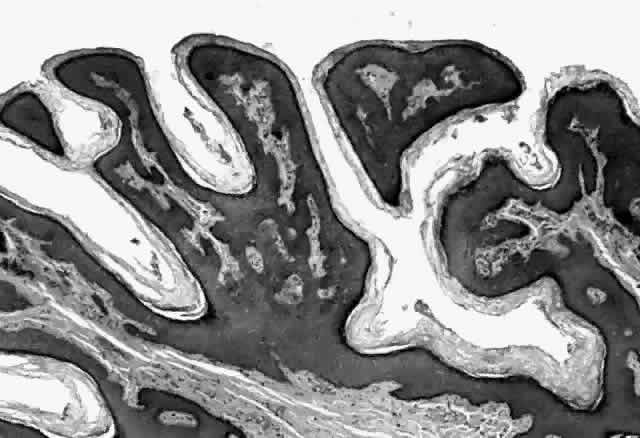

HPV-induced conjunctival squamous papillomas demonstrate papillomatosis, acanthosis, and koilocytosis (Fig. 6). Because they are mucous membrane lesions, those of the conjunctiva and lacrimal sac show no granular cell layer but will show keratinization if they are large or exposed (Fig. 7). In our experience the frequency of koilocytes is variable, even in lesions almost certain to be viral (Fig. 8). Scattered inflammatory cells may be present in the cores or epithelium. Virus can be detected immunohistochemically in the nuclei of the cells (Fig. 9).

Molluscum contagiosum is a papule with lobular downgrowth of epithelium into the dermis and a central “crater” on the surface (Fig. 11). The epithelium and infected cells demonstrate hyperplasia. Basal cells divide more rapidly (6.1 day turnover decreasing to 3.4 days) and infected cells show more rapid migration through the epithelium as well as cessation of host DNA transcription.121,122 Each lobule demonstrates a progression from base to top. The malpighian cells contain eosinophilic elementary bodies (Fig. 12). These coalesce to form a hyaline molluscum body (HendersonPaterson body).123 The cytoplasmic molluscum bodies increase in size until they distort and displace the nucleus, sometimes becoming larger than the original host cell (Fig. 13). At the top of the lobule in the granular cell layer, the Henderson-Paterson inclusion body changes from eosinophilic to basophilic. When the overlying stratum corneum loses its integrity, the crater is formed (see Fig. 10). Microdissection revealed124 and scanning electron microscopy confirmed125 the presence of a sac surrounding the viral inclusion body within each cell, which has been speculated to provide an immunologically sheltered site for viral reproduction.

Fig. 11. Molluscum contagiosum, histology. Low-power view of lobular epithelial downgrowth and central umbilicated crater. (Original magnification × 50)